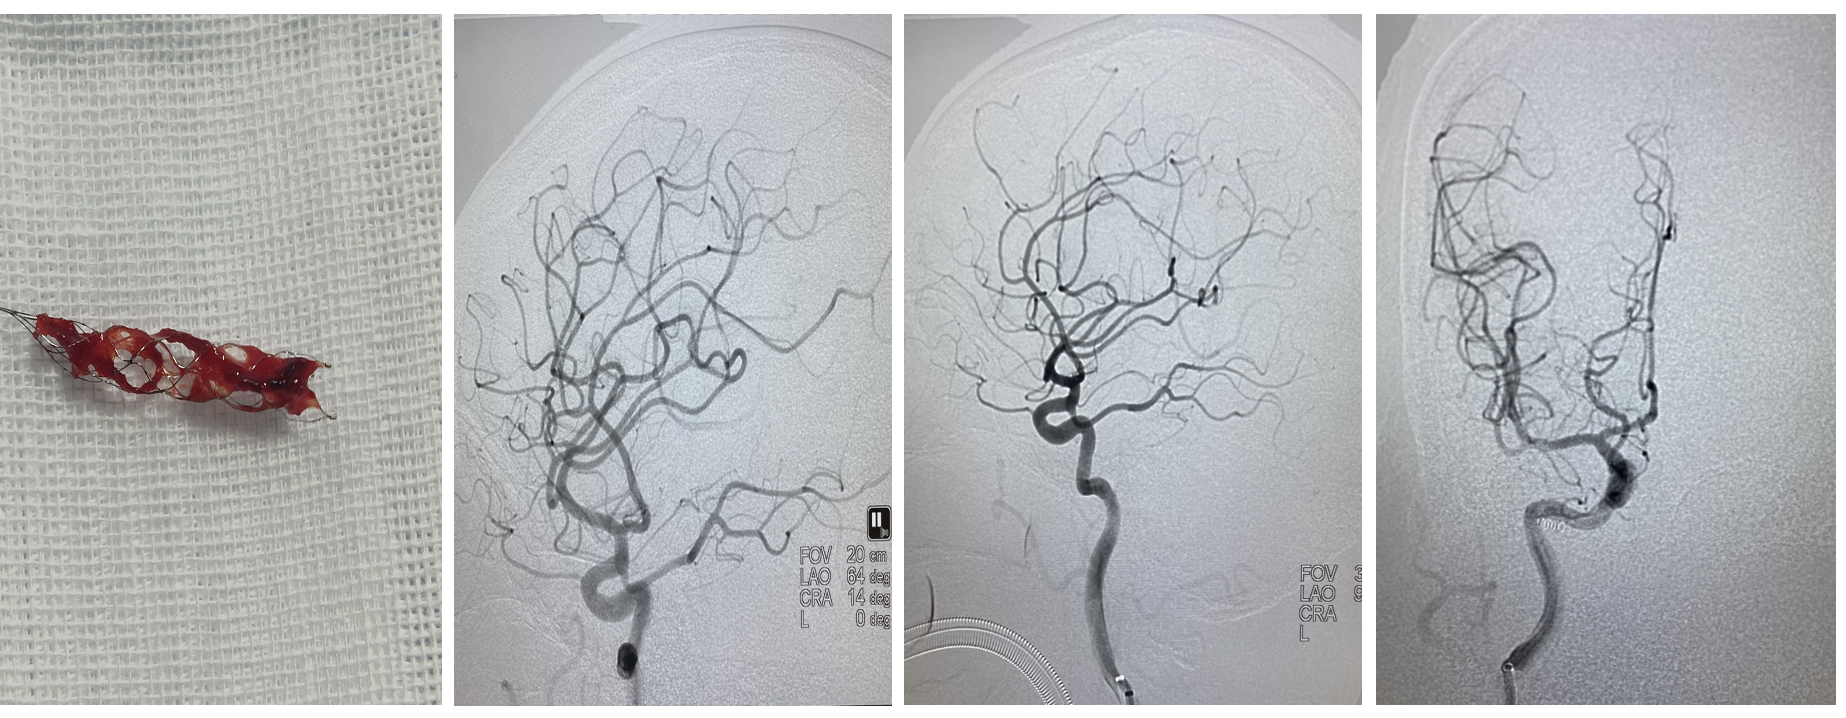

6、关闭滴注,中间导管到达M2分叉部,缓慢轻拉支架入中间导管整体撤出体外,可见支架远端附着血栓。 术后即刻造影,闭塞分支血管再通,M2闭塞处的可疑血栓消失,至此4支血管全部通畅,血流3级,结束手术。

7、术后情况:术后12小时,患者凝视消失,语言流畅,左侧肢体肌力恢复至3级,头颅CT复查:右侧颞叶无症状少量出血灶,散在低密度影。次日,左侧肢体肌力恢复至4级。

此病例是典型的MeVO,闭塞部位为右侧M2段上干的远端,我们选择心玮较小的取栓支架4-20进行取栓是可行的,抽拉结合取栓后3D造影,发现原有闭塞的部位就在上干分叉部,且共有4个分支,取通3支,还有1支向额叶供血的分支未通,术中一度纠结,到底要不要继续取分支血管?分析认为,分支闭塞应该是继发的血栓逃逸,该病例给了静脉溶栓,血栓负荷量并不是很大,而且患者术前有失语的症状,能开通那是锦上添花,就看能否超选成功,起始部虽然成直角,中间导管到位很高,超选倒是容易,但血管还是很迂曲,直径应该在1mm以下,小心释放心玮4-20支架,部分释放在中间导管内,谨小慎微,只想尝试一把,结果运气很好,血栓成功取栓,4支血管全部通畅,术后迅速改善了患者的症状。